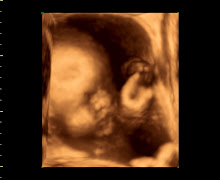

I went this morning for our Ultra screen Exam which went well- (it screens for chromosomal abnormalities, etc) they used the abdominal ultrasound this time and it was hard to see the baby because apparently my uterus is tilted and more in the back – the photos from this session are a total blur (the doctor said it will move to the front in a week or two and I’ll be showing more at that time). Then the nurse brought us in to try and hear the heartbeat, she was unsuccessful and brought in another nurse to try and help get a fetal heartbeat. Both nurses weren’t able to since my uterus is tilted and back further, so the doctor came in and tried his hand at it… he was able to hear movements and a few flutters but nothing to relive us so he offered a trans-vaginal ultrasound. Once we got moved into another room for the 3rd time- we got hooked up to the vaginal ultrasound. Everything was perfect (sigh of relief)! We were able to see his heart beating normally and he kept moving his arms/feet around like he was playing soccer or dancing- it amazing. The doctor was able to get 4 photos during this time.

His whole body, head, arms and feet.